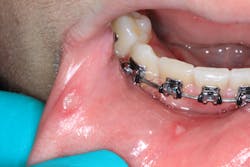

A healthy 16-year-old male presented with this chief complaint: I got my wisdom teeth out five days ago, and I can’t eat or swallow; it hurts. I have bumps all over in my mouth.

Clinical assessment revealed multiple white lesions with red borders salt-and-peppered in a generalized fashion throughout the entire oral cavity. The gum tissues were swollen and any light palpation/touching of the lesions resulted in bleeding and pain. See clinical photos below.

Acute herpetic gingivostomatitis